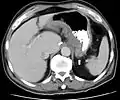

CT scan showing Crohn's disease in the fundus of the stomach